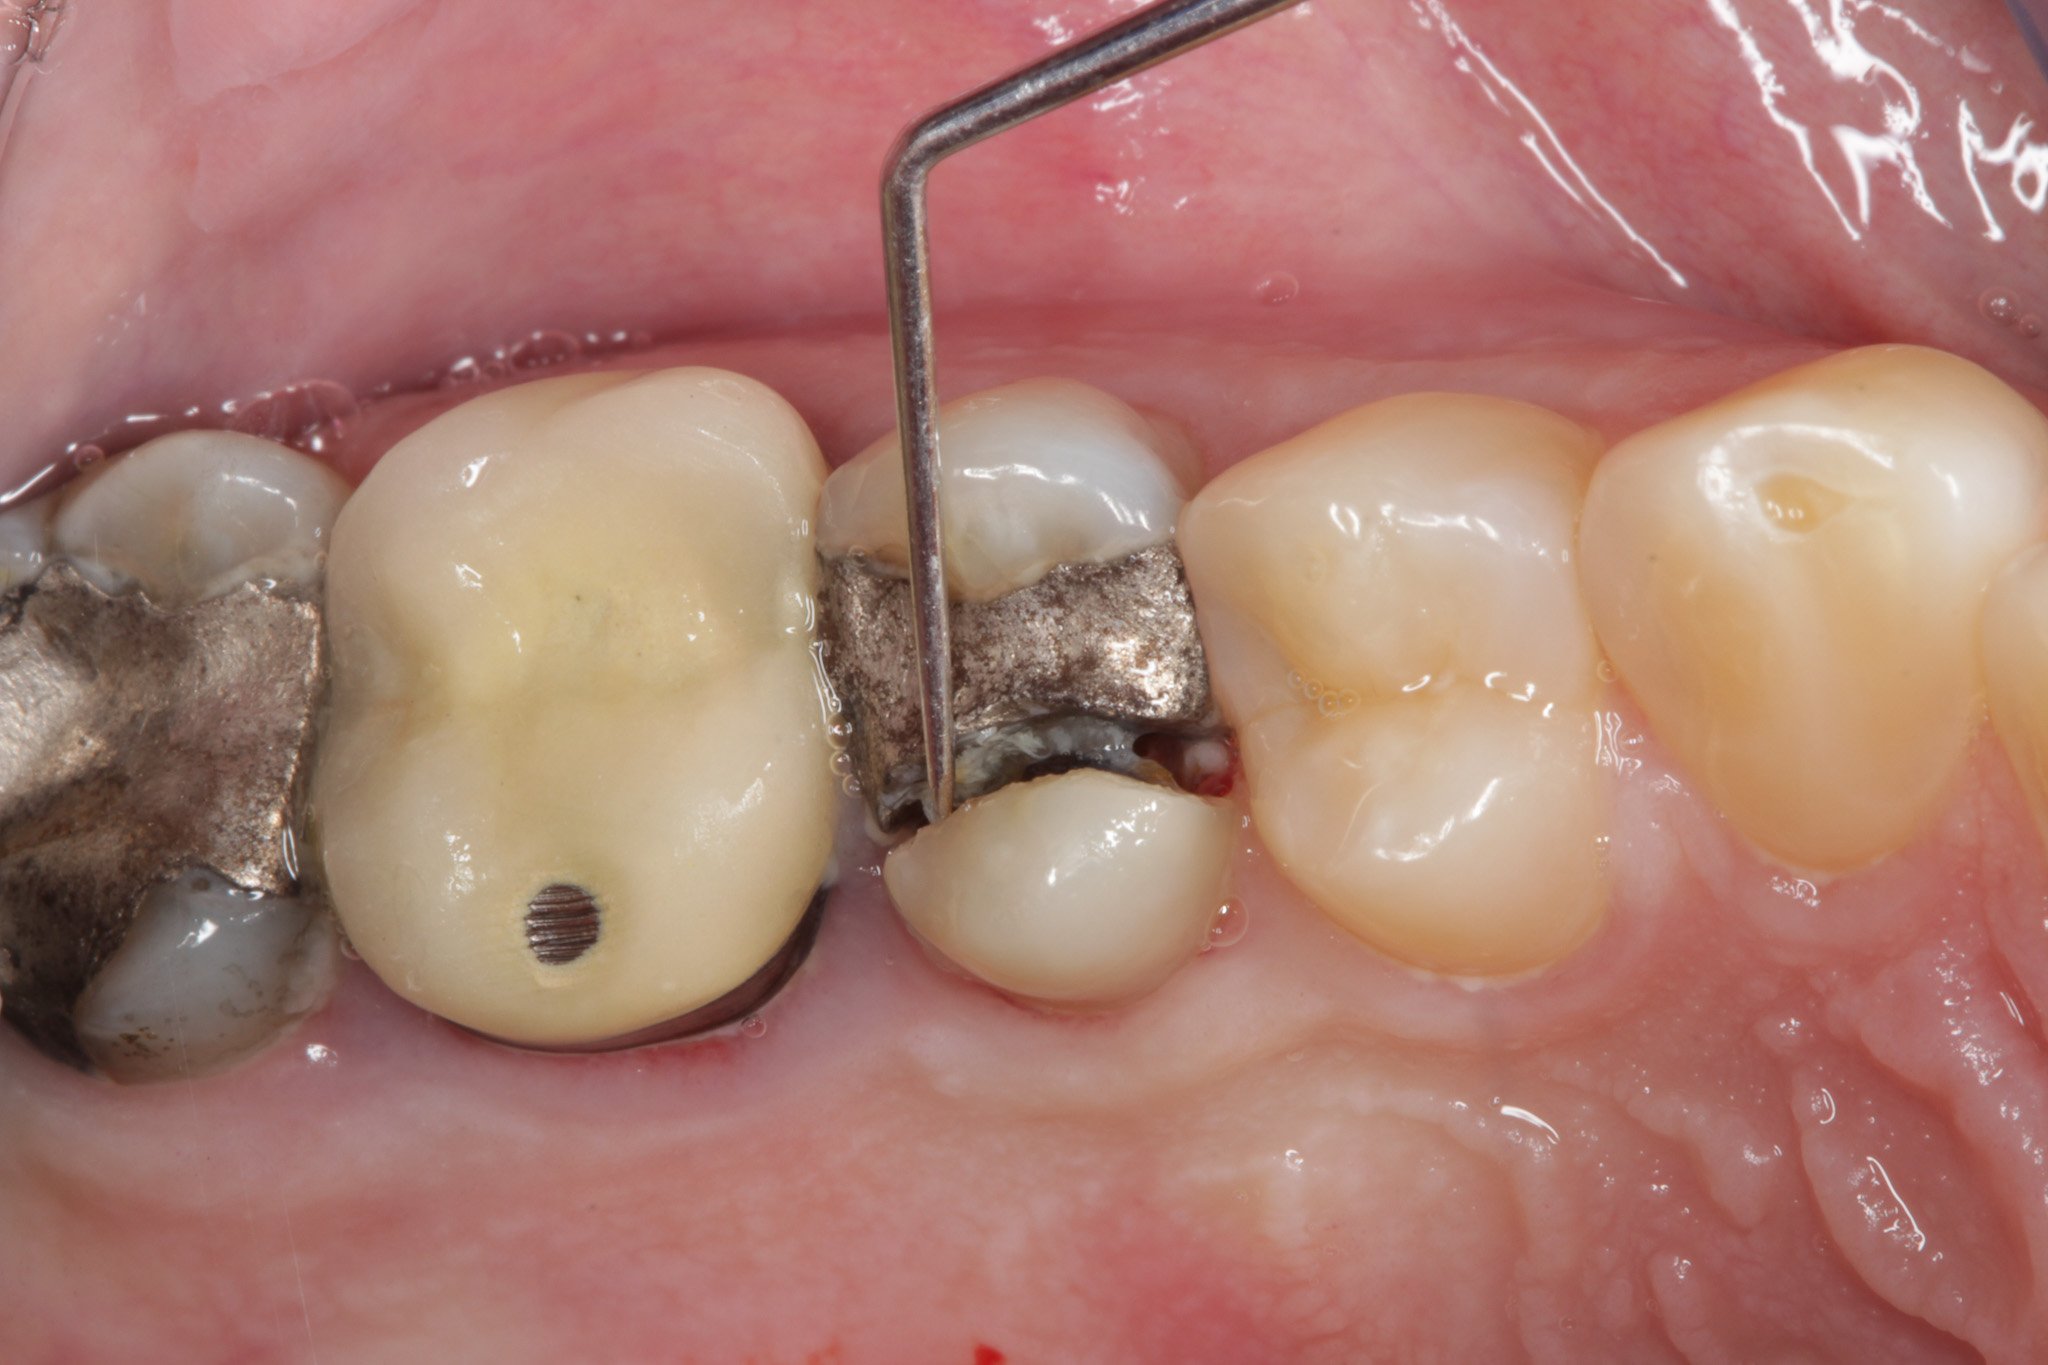

Một số trường hợp bị vỡ do miếng trám đã hết tuổi thọ

Những miếng trám bị bung, cần được trám lại sớm để tránh hậu quả nặng nề hơn